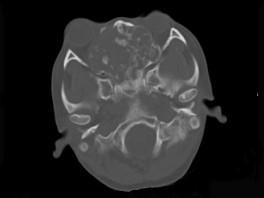

问题 男性,28岁,因鼻塞、头痛1年余,鼻窦CT扫描如图所示,请选择正确的描述与结论 ( )

选项 A、考虑鼻窦骨瘤 B、考虑为鼻窦软骨瘤 C、肿块内密度不均,有较多致密钙化影 D、窦壁及颅底骨质破坏 E、双侧上颌窦、筛窦、鼻腔及蝶窦内见软组织肿块影

答案 BCDE